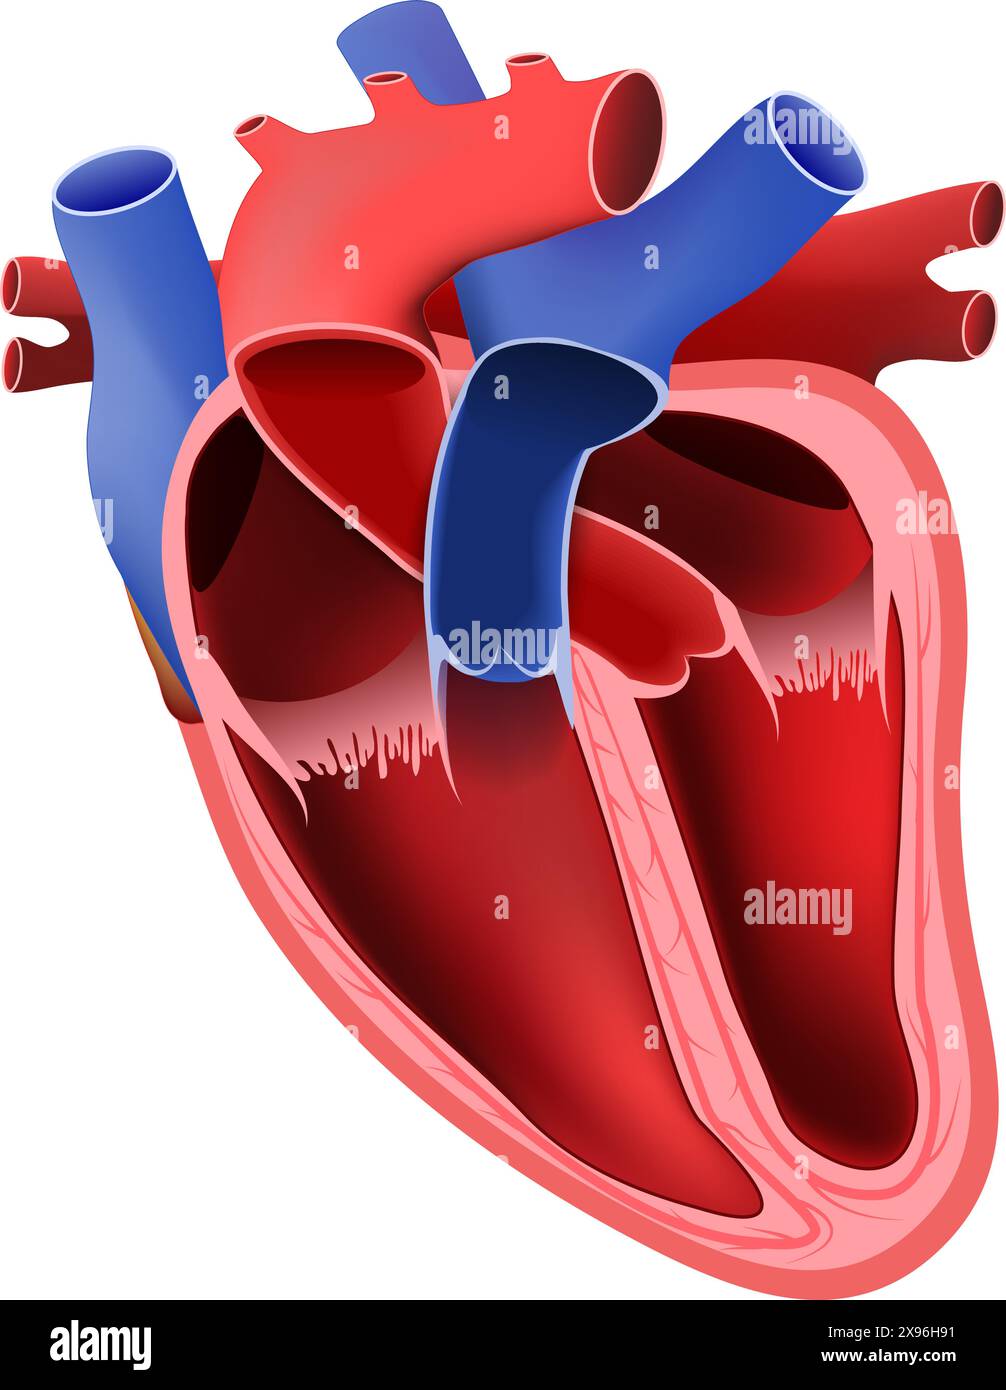

Heart anatomy. Part of the human heart. vector illustration. Stock Vectorhttps://www.alamy.com/image-license-details/?v=1https://www.alamy.com/heart-anatomy-part-of-the-human-heart-vector-illustration-image608040077.html

Heart anatomy. Part of the human heart. vector illustration. Stock Vectorhttps://www.alamy.com/image-license-details/?v=1https://www.alamy.com/heart-anatomy-part-of-the-human-heart-vector-illustration-image608040077.htmlRF2X96H91–Heart anatomy. Part of the human heart. vector illustration.